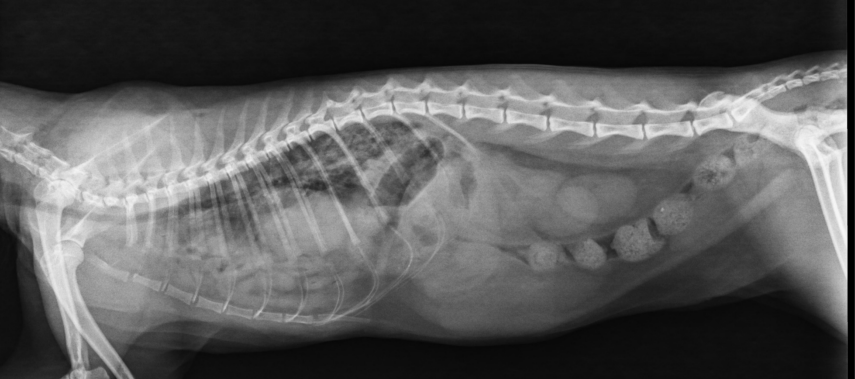

ÚTERO

- Visible cuando distendido: estructuras tubulares tortuosas en abdomen caudoventral.

- Causas:

- Fisiológico: gestación temprana

- Patológico: piómetra, hidrómetra, mucómetra, neoplasia, absceso de muñón

- Gestación: mineralización fetal visible 40–45 días.

- Muerte fetal (Si encontramos gas con los fetos), momificación, distocia (Problemas para el parto).